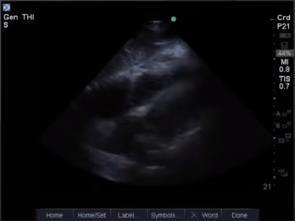

Heart Epicardial Fat 1 Image